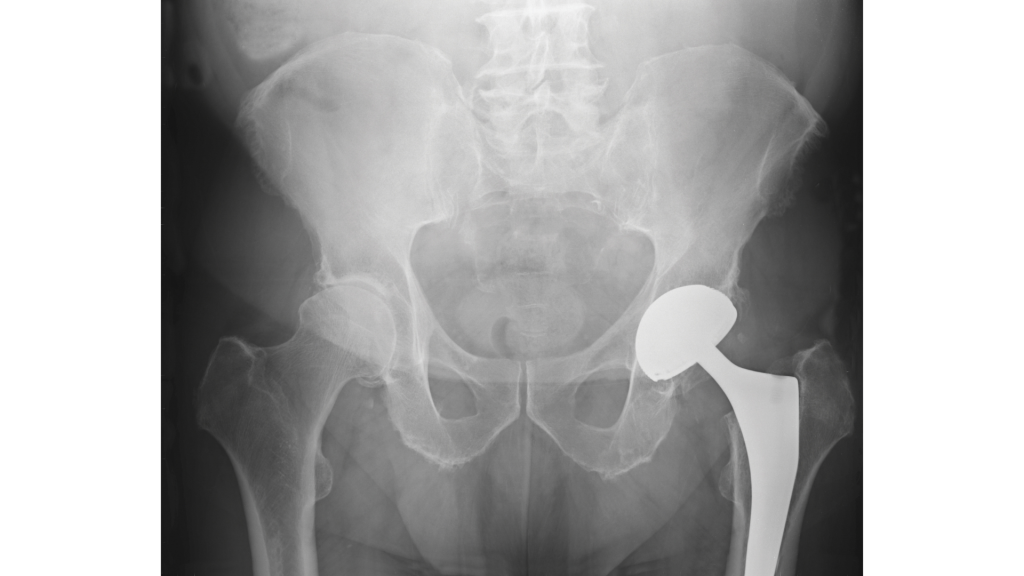

Nei casi di coxartrosi moderata o severa che non abbiano risposto in modo significativo alle terapie conservative, è fondamentale richiedere una consulenza ortopedica. In molti casi, si potrà procedere con l’indicazione per un trattamento chirurgico, come la chirurgia protesica.

Esistono due principali tipologie di intervento: l’artroprotesi, che prevede la sostituzione dell’acetabolo e della testa femorale, e l’endoprotesi, che riguarda la sostituzione solo della componente femorale.